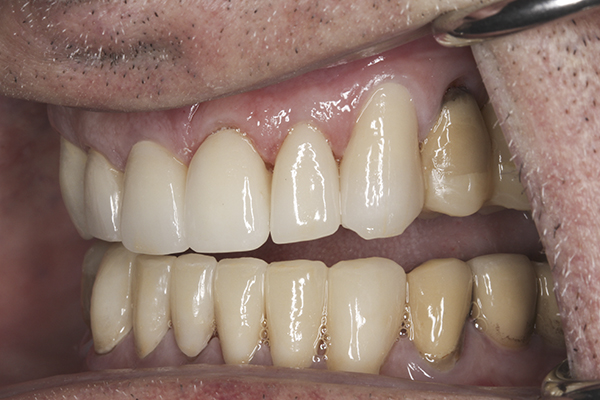

(23.) Provisionals, right lateral, closed view.

Figure 23

(24.) Provisionals, anterior, closed view.

Figure 24

(25.) Provisionals, left lateral, closed view.